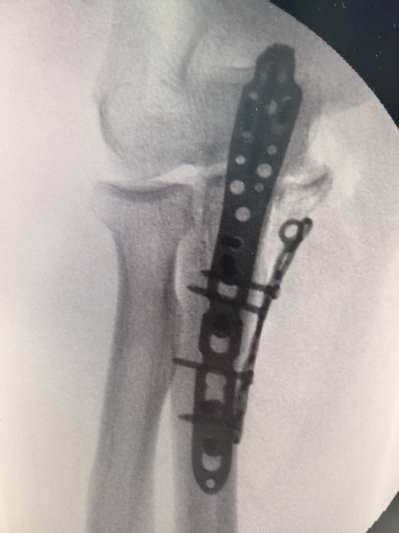

一名69岁男性,因不慎撞伤导致肘关节明显肿胀疼痛,不能活动,当即来苏州九院就诊。行x线检查后示尺骨近段粉碎性骨折。经过吴卫东、黄晟医生仔细读片后诊断为经尺骨鹰嘴孟氏骨折。骨折断裂情况严重,尺骨鹰嘴、尺骨冠突骨块分离,同时存在肘关节内侧不稳定,病情复杂,手术难度非常大。

此次手术,借助先进3D打印技术,精确**了患者骨折部位的骨骼结构,为手术提供了直观、详尽的参考。经过吴卫东、黄晟手术团队的努力,患者的粉碎性骨折得到了有效治疗,术后恢复良好。